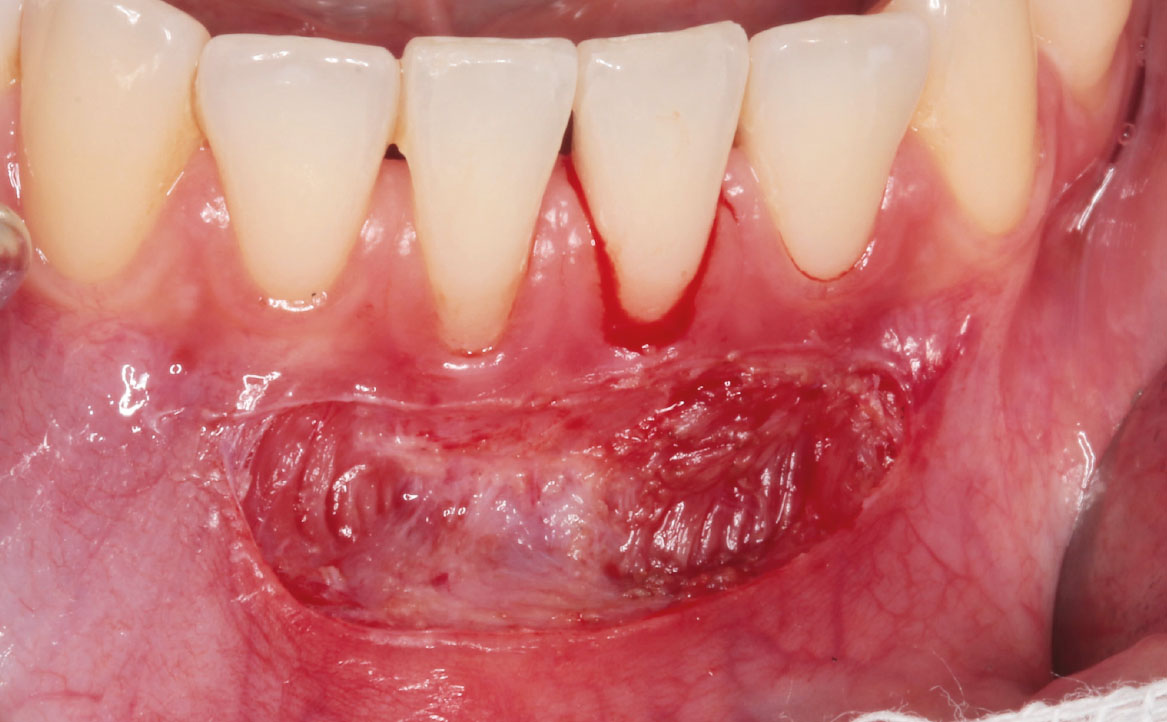

Previa anestesia loco-regionale plessica con lidocaina, è stata eseguita un’incisione parallela rispetto alla cresta alveolare e scollamento della mucosa mediante un laser neodymium yttrium aluminum garnet laser (Nd:YAG, 1064nm, 3.75W, 75Hz) (fig. 4-5).

Il vantaggio dell’impiego del laser nella procedura descritta risiede nel suo effetto fototermico.

In particolare, l’azione diretta del raggio nei confronti dell’emoglobina e della melanina e il trasferimento di calore ai tessuti irradiati determinano la coagulazione dei vasi sanguigni contestuale al taglio, proprietà che permette di mantenere un’ottima visibilità del campo operatorio (3). Inoltre, lo scarso assorbimento in acqua della radiazione generata dal laser Nd:YAG permette al raggio luminoso di attraversare agevolmente i tessuti, penetrando fino a 4-5 mm di profondità (3,4). La dispersione della luce nei tessuti (effetto scattering) fa sì che il laser agisca anche a livello dei tessuti limitrofi all’incisione, a livello dei quali svolge un’azione fotobiomodulante, favorendo così una guarigione più rapida della ferita chirurgica.